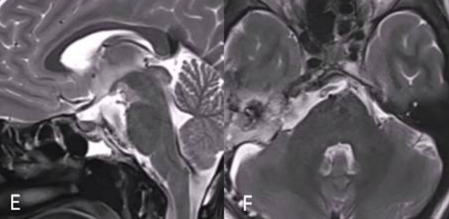

两个月后,潇潇的身体恢复良好,于是,福教授又为她进行了Ⅱ期手术。这一次采取的是右侧的mini经岩骨入路,最终实现全切,且无任何新发神经功能缺损。

然而,对于狡猾的脊索瘤而言,全切相当于为整体的治疗开了一个好头,后续仍然要进行辅助治疗,才能最大程度延缓复发。于是,在福教授的建议下,潇潇开始接受质子束治疗(PBT)。在5个月的随访期间,潇潇并未出现不适,神经系统检查结果十分正常,而且头面部的美观效果也非常好,这也得益于福教授所采取的两个微创入路。